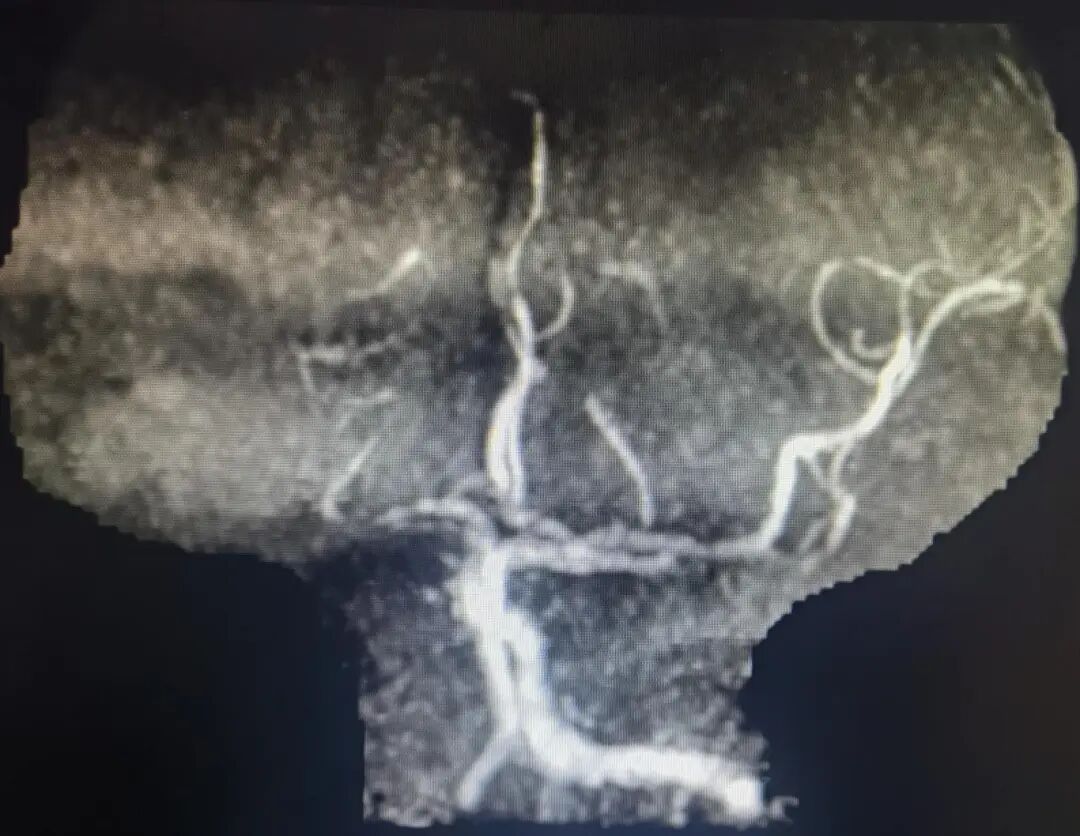

Right internal carotid angiography showed occlusion of the right ICA, with no collateral circulation in the right ACA or right MCA, and no compensatory blood flow in the surrounding area.

Post-aspiration angiography demonstrated good visualization of the right MCA and ACA.

The right MCA, ACA, and their branch arteries were well visualized, with antegrade flow of TICI grade 3 and no signs of acute vascular occlusion.